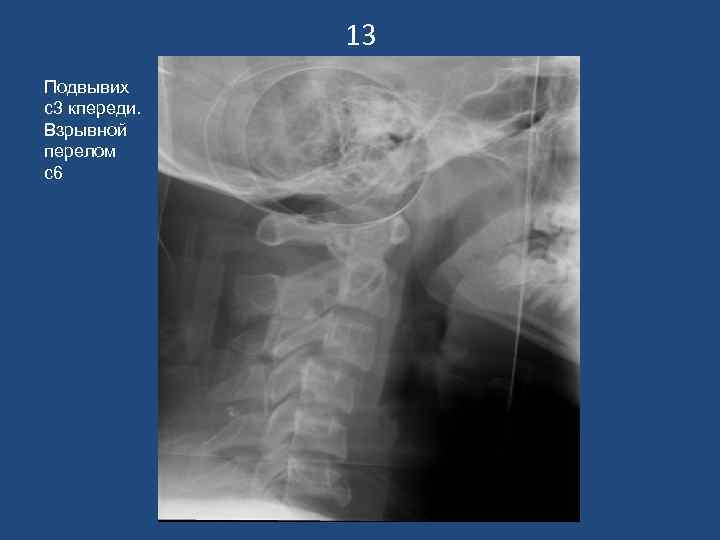

13 Подвывих с3 кпереди. Взрывной перелом с6